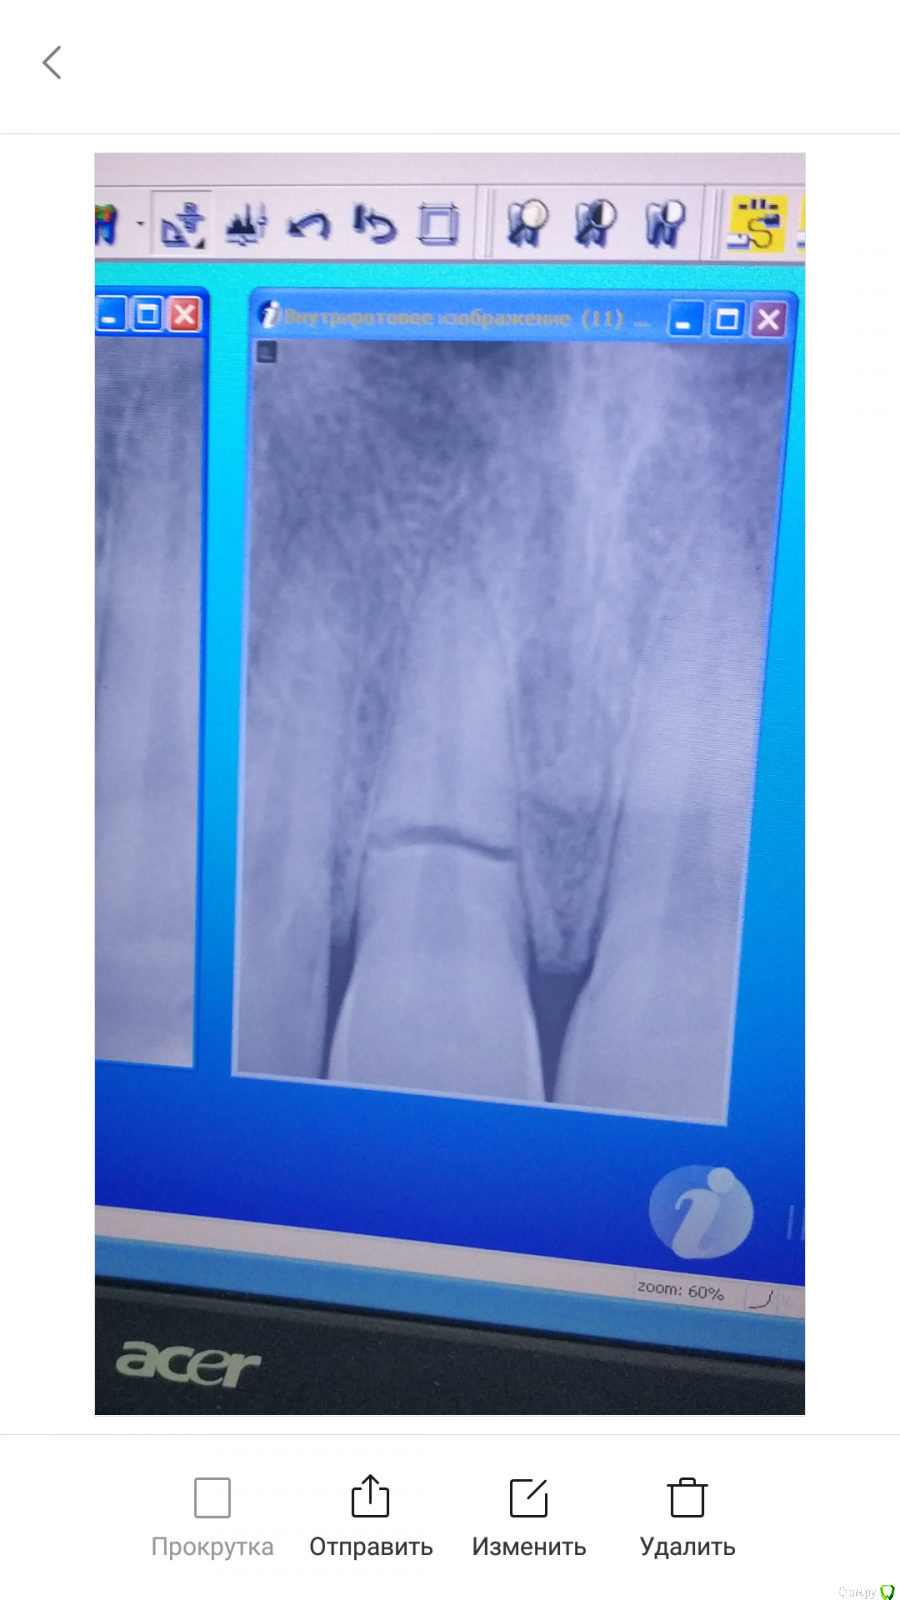

Artacc Опубликовано 25 февраля, 2019 Автор Поделиться Опубликовано 25 февраля, 2019 http://forum.stom.ru/topic/20613-sovety-patcientam-obiazatelno-k-prochteniiu/Прикрепил снимок 1 Ссылка на комментарий

Kolchanov Опубликовано 25 февраля, 2019 Поделиться Опубликовано 25 февраля, 2019 Если не будет некроза с последующим инфицированием, то будет либо облитерация, либо заместительная резорбция, либо и то и другое одновременно. Варианты можно посмотреть в моих темах Давняя травма и Давняя травма2. Тут только по рентгенограмме нельзя дать оценку, надо провести холодовую пробу, оценку подвижности коронального фрагмента, есть ли нарушение эпителиального прикрепления. В каких-то случаях можно потянуть, под пристальным наблюдением, в каких-то лучше сразу удалить. Ссылка на комментарий